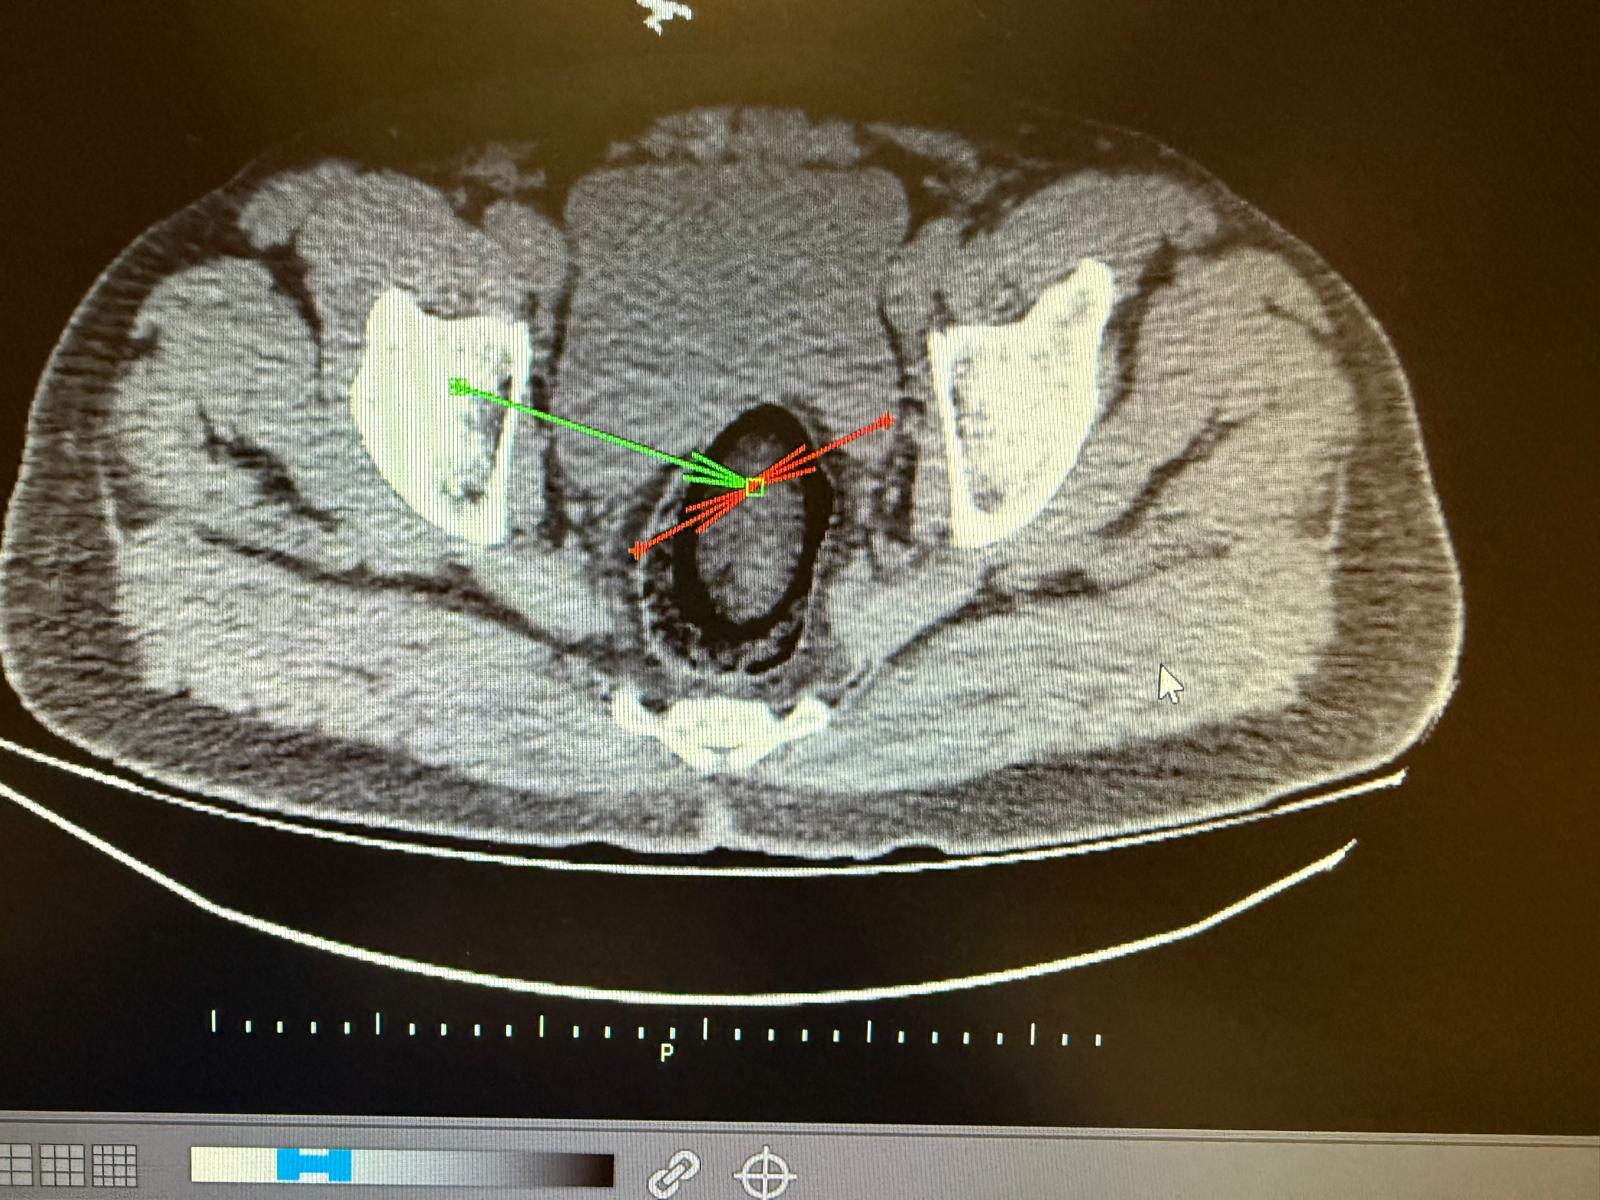

Kars Harakani Devlet Hastanesi'ne götürülen F.H.'nin çekilen röntgeninde, makatında uyuşturucu tespit edildi. Cerrahi operasyonla makatından 105,98 gram metamfetamin metamfetamin çıkarıldı. Emniyetteki işlemlerinin ardından adliyeye sevk edilen şüpheli, çıkarıldığı hakimlik tarafından tutuklandı.